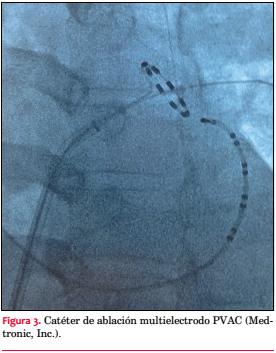

Constantemente nuevas tecnologías se van desarrollando en el campo de la electrofisiología con el objetivo de mejorar la seguridad y eficacia de los procedimientos. En el caso de la ablación de la FAP, donde el objetivo es el aislamiento de las VP, sin la realización de líneas de ablación adicionales, nuevos catéteres de ablación circulares (single shot) se encuentran disponibles. Estos han demostrado reducir el tiempo de procedimiento y de fluoroscopía manteniendo la misma eficacia y seguridad que la ablación convencional “punto por punto”. El Pulmonary Vein Ablation Catheter (PVAC, Medtronic, Inc) es un catéter decapolar que al asentarse alrededor de las venas registra la actividad eléctrica permitiendo simultáneamente liberar radiofrecuencia de forma ciclada bipolar y monopolar, generando lesiones circunferenciales alrededor del ostium (figura 3)(48,52). Siguiendo el mismo concepto, pero usando un sistema de irrigación con la idea de evitar la formación de coágulos en la interface catéter-tejido, el nMARQ (Biosense Webster) es otro catéter multielectrodo circular disponible(49,53).